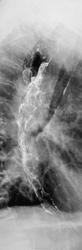

Глядя на картинки, вспомнила пациента с инфильтративной формой злокачественной лимфомы в желудке. А что в клинике? Возраст? Еще подумалось о болезни Крона, но сомневаюсь. Непаханое поле для эндоскопистов (биопсию имею в виду).

Возраст преклонный, сильно похудел, твердая пища не проходит...

Да, для эндоскопистов работа. Изменения пищевода могут быть и функционального характера. Но с учётом возраста думается о плохом. Похоже в ДПК есть дивертикул. Заброс бария в трахею

Добрый вечер. Контраст в трахею попал через свищ  или пациент поперхнулся во время исследования?

Пациент выпил всего два глотка, все время подкашливал.

Часть желудка в горизонтальном положении вышла за купол диафрагмы?

Хмм, изменения в пищеводе по-всякому органические, скорее всего рак.. Только вот что с желудком? Почему-то его так скрутило.., в анамнезе есть язвенная болезнь, может быть улиткообразная деформация?

зы. Похоже, что дно желудка тоже вовлечено..

Еще приходит мысль о бульбарном синдроме, для рака такая протяженность, по-моему, маловероятна.

Пациенту произведена ФГДС, диагностирован рак пищевода...,